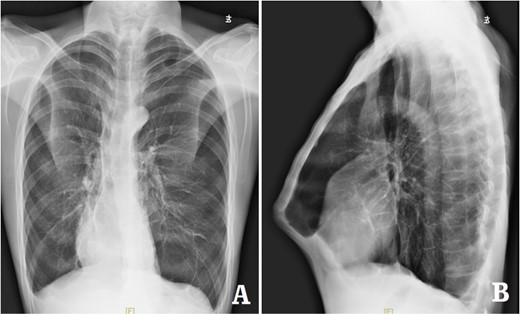

The patient was a 29-year-old male. He was found to have protrusive deformity on the anterior chest wall since childhood. The deformity was not serious in early years, but worsened after adolescence, with the lower part of the sternum protruding at an acute angle. At the age of 25, he developed right spontaneous pneumothorax and received surgical treatment at local hospital, but his thoracic deformity was not treated. As the deformity continued to worsen, which seriously affected the appearance of the chest wall, the patient was admitted to our hospital for surgery. Preoperative physical examination showed that the anterior chest wall was protrusive seriously, with a sharp tip protruding forward. The rib arches on both sides were slightly depressed (Fig. 1). Imaging examination showed that the anterior chest wall was protrusive, and the lower end of the sternum was at the forefront of the protrusion. His heart moved to the right, and the rib arches were slightly depressed (Figs 2–4). The operation was performed under general anesthesia. Two longitudinal incisions were made on both sides of the chest wall respectively. The incisions were located between the front axillary line and the median axillary line, with the length of ~5 cm. The chest wall muscles were dissected to expose the ribs in the incisions. Two tunnels were made on the highest plane of the protrusion, with interval of 3 cm. The tunnels were located in the deep layer of the chest wall muscles and bone structures. Two steel bars were inserted into the tunnels to flatten the front protrusion with their median parts, and then, both ends of the steel bars were fixed on the ribs at the lateral chest wall. The above operation was the main content of Wenlin procedure [1, 2, 5]. After this procedure was completed, the lower part of the chest wall showed obvious depression, especially in the middle of the rib arches. Then, Wung procedure was performed [6]. A third tunnel was made at the plane passing the midpoint of the rib arch, which passes through the bilateral thoracic cavity. The third steel bar was inserted into the tunnel. After the steel bar was rotated and fixed to the ribs, the depression was supported totally. The incisions were closed, and the operation was completed. The deformity of anterior chest wall disappeared completely after the operation (Fig. 5). The operation time was 75 min. The intraoperative bleeding volume was 40 ml. Postoperative X-ray examination showed that the bars position was normal (Fig. 6). He was discharged 7 days after operation. Follow up for 1 year showed satisfactory recovery. The steel bars were taken out 1 year after the operation, and the appearance of the thorax was normal and there was no recurrence (Fig. 7).

X-ray examination before operation. (A) Posteroanterior radiograph; and (B) lateral radiograph.